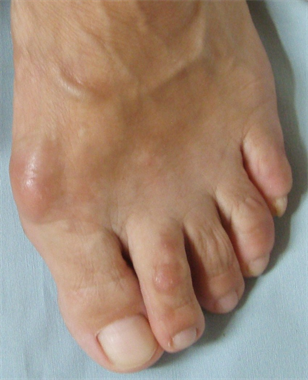

Figure 24. Patient Nr. 4: Preoperative clinical view.

Figure 25. Patient Nr. 4: Postoperative clinical view.

Figure 26. Patient Nr. 4: Postoperative clinical view.